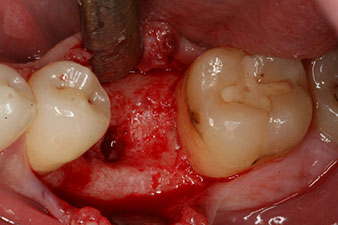

Abb. 2: Sechs Wochen später zeigt sich eine nur unvollständig ossifizierte Alveole im Bereich der mesialen Wurzel.

Sechs Wochen nach Extraktion zeigte sich jedoch nach Präparation des Mukoperiostlappens im Bereich der ehemaligen mesialen Alveole eine unvollständige Ossifikation.

unvollständige Ossifikation